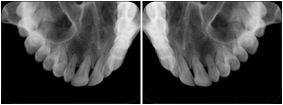

Intra-oral radiography typically involves acquisition of multiple images of various parts of the dentition. Many digital radiographic systems offer customized templates that are used for displaying the images in a study on the screen. These templates may also be referred to as mounts or view sets. The Structured Display Object represents a standard method of encoding and exchanging the layout and intended display of Structured Displays. A structured display object created in this manner could be stored with a study and exchanged with images to allow for complete reproduction of the original exam.

3. A dental provider wishes to capture a series of DICOM IO images for the patient’s dentition. The tooth morphology, teeth are divided into molars, premolars, canines and incisors, and a number of images for each jaw. The anatomic information was captured utilizing the triplet of schema. This standard code sequence is based on ISO 3950-2010, Dentistry - Designation system for teeth and areas of the oral cavity.

In most standard cases, images are oriented in structured layouts. These structured displays are useful to be shared between providers for reference purposes.

Table OO.1.1-1 shows structured display standard templates, where Viewset ID is based on the Japanese Society for Oral and Maxillofacial Radiology (JSOMR) classification provided by JIRA (Japan Medical Imaging and Radiological Systems Industries Association, www.jira-net.or.jp). Expected or typical teeth to be imaged location, region and designation codes are based on ISO 3950-2010, Dentistry - Designation system for teeth and areas of the oral cavity. For all the hanging protocols listed in OO.1.1-1, the value to use for Hanging Protocol Creator (0072,0008) is "JSOMR" and the value to use for Hanging Protocol Name (0072,0002) does not include "JSOMR" (e.g., "DL-S001A", not "JSOMR DL-S001A").